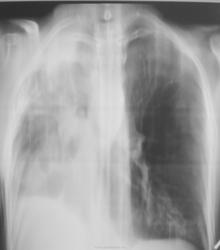

По рентгенограммам фиброторакс как бы неполный, однако, на представленных томограммах правый главный бронх в виде культи, но нечётко видимой. И металл. зажимы в срезы не попали. Там точно всё удалено?

Левое лёгкое с патологией и в нижней доле и в верхней.

Неоднозначно всё

Согласно документам - пульмонэктомия.

Ну пульмонэктомия-значит пульмон эктомия , ничего нового.Только надо иметь ввиду грубое смещение органов средостения и медиастинальная грыжа.

С медиастинальными грыжами понятно. А что ещё светится на месте удалённого лёгкого? При фибротораксе такого не может быть. Когда была операция? И клиники хоть ложку надо.